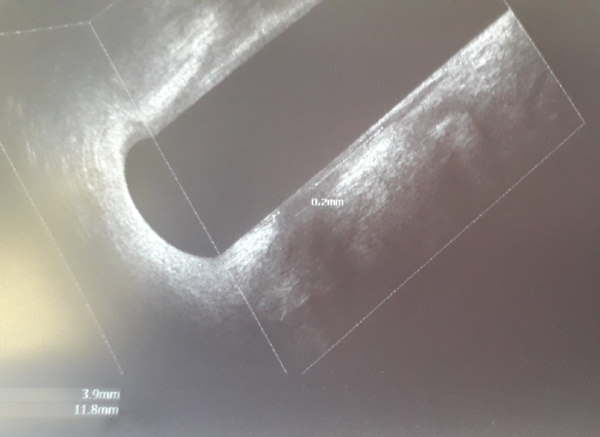

L'immagine in 3D consente ulteriori osservazioni.

L'ecografo può raccogliere tutte le immagini e ricreare una ricostruzione in 3D che attraverso il touch screen consente di muoversi anche secondo il piano longitudinale e frontale. Il 3D consente di vedere la lunghezza di una lesione o lo spessore dei muscoli del retto.

Le immagini offerte dala RMN hanno una definizione eccellente per lo studio della morfologia e i rapporti fra le masse/lesioni e i tessuti circostranti. L'ecografia aggiunge delle informazioni in più dato che consente di identificare tumori più piccoli e che sono vicini all'ano.

L'ecografia agli occhi di un "profano" è un insieme di macchie grigie, ma nelle mani dello specialista consente al chirurgo di vedere i rapporti fra il tumore e i tessuti, i vasi e i linfonodi circostanti.

Nello studio delle fistole è possibile vederne il miglioramento verso la guarigione o nella fase infiammatoria identificarne la ramificazione e poter decidere la migliore strategia d' intervento.